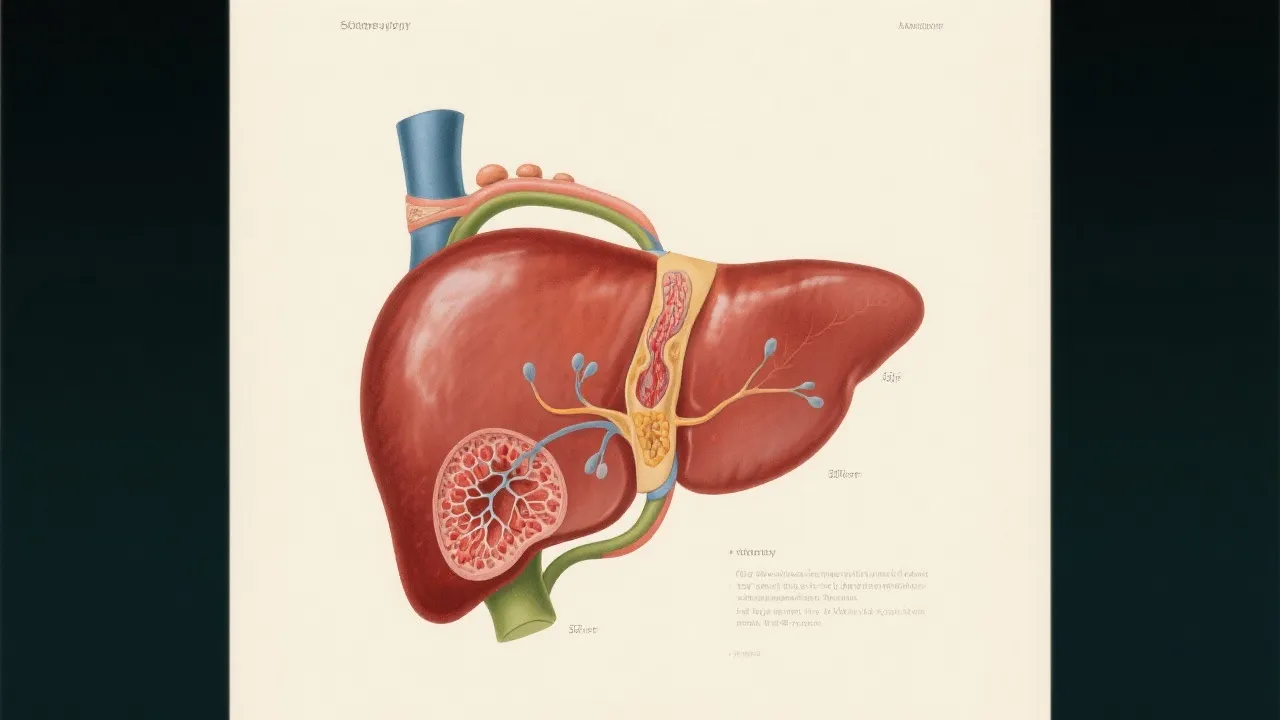

The liver, a vital organ, is responsible for numerous metabolic, detoxifying, and regulatory functions. It processes nutrients, secretes bile, synthesizes proteins, and acts as a blood filter, clearing toxins and waste products from the bloodstream. Any disruption in the liver's orderly functioning can result in severe health issues, and Seimc Hepatitis is one such condition.

This condition is characterized by inflammation induced by viral, autoimmune, or toxic agents. The viral agents responsible may not be as well-documented as those causing other types of hepatitis. Still, researchers suspect potential culprits that may induce an inflammatory response without the widespread recognition seen in Hepatitis A or B. A plethora of factors contribute to Seimc Hepatitis's complexity, including genetic predispositions, environmental influences, and often overlapping symptomatology with other liver conditions.